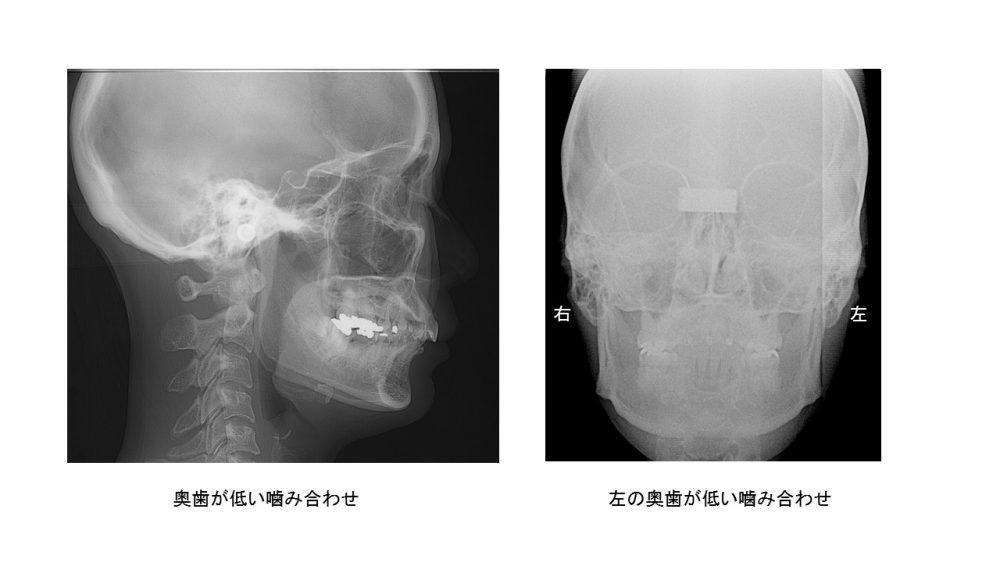

奥歯の高さが低いと、見た目はそこまで悪くなくても下顎が後ろに下がり、横から見た顎の角度が急になります。

下のレントゲンを参照

左のように顎の角度が急な人は顎が奥に入りやすく、頚椎の形態まで変化してしまいます。つまり奥歯が低い噛み合わせといえます。

片方の奥歯だけ低くなると、顎が左右的に曲がります。こうなると単純ではない様々な体調不良が出てきます。(詳しくはこちら

左は奥歯も前歯も低い噛み合わせ、右は左右で高さが違う噛み合わせです。